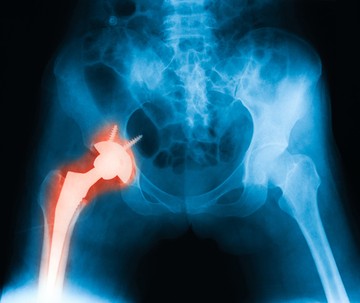

A jövő csontpótlása kinyomtatott implantátummal